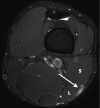

Background: Injury to the distal musculotendinous T junction (DMTJ) of the biceps femoris is a distinct clinical entity that behaves differently from other hamstring injuries due to its complex, multicomponent anatomy and dual innervation. Injury in this region demonstrates a particularly high rate of recurrence, even with prolonged rehabilitation times.

Results: Of the 106 acute injuries to the DMTJ of the biceps femoris, isolated injury to the long head component was the most common (51%), with both components involved in [round 42.5% to 43%] of cases. Isolated injury to the short head component accounted for 7% of cases. The recurrence rate for reinjury to the DMTJ was 54% in this series. The date of prior injury was known in 45 of 57 recurrent cases, with 34 of these reoccurring within 3 months (76%) and 40 reoccurring within 12 months (89%). The recurrent injury was of a higher grade than the prior injury in 22 of 44 instances (50%), the same grade in 16 instances (36%), and a lower grade in 6 instances (14%). Thus, 86% of recurrent injuries were of the same or higher grade than prior injury.

Conclusion: These results suggest that high-risk muscle injuries, such as that to the DMTJ of the biceps femoris, should be evaluated using MRI to determine the structural components involved and to assess the extent and severity of injury.